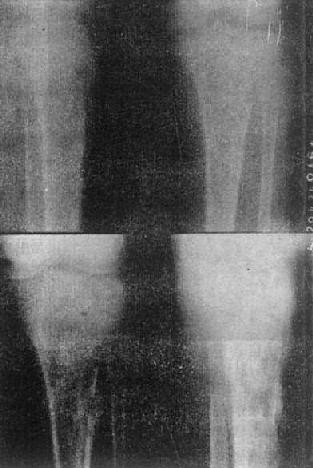

胫骨慢性化脓性骨髓炎,花边状骨膜增生

图2-1-12 胫骨慢性化脓性骨髓炎,花边状骨膜增生

胫骨慢性化脓性骨髓炎

图2-1-13 胫骨慢性化脓性骨髓炎

上图可见骨破坏及骨膜反应,有死骨形成。下图为半年后,死骨更为明显

骨质坏死多见于慢性化脓性骨髓炎,也见于骨缺血性死和外伤骨折后。